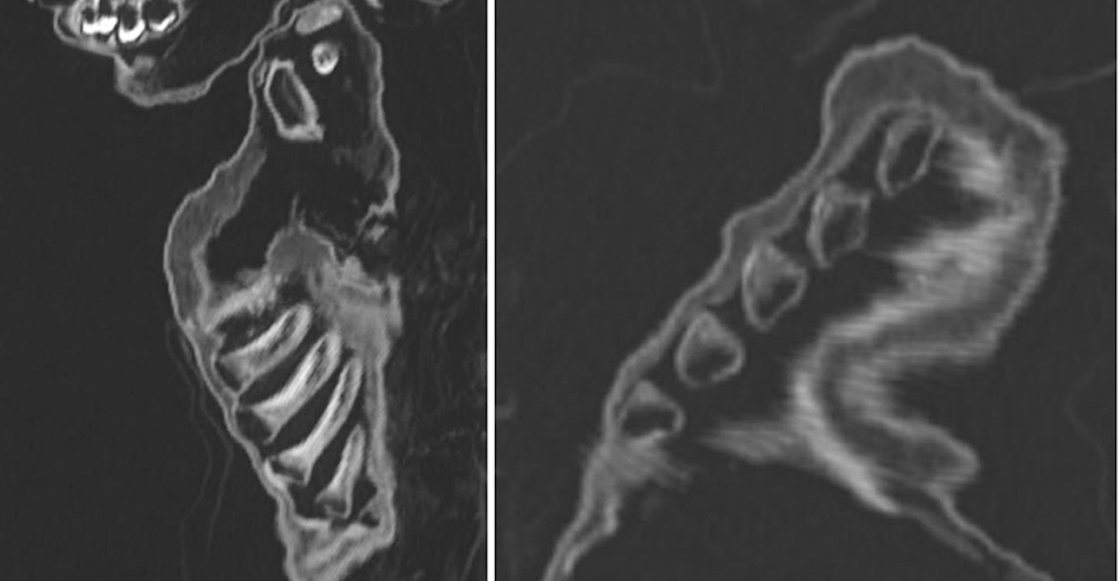

¿Cómo llegaron a esa primera conclusión? Antes de este análisis, ya habían hecho una autopsia al cuerpo del niño por malformaciones en las costillas.

Justo este fue el elemento que hizo que pensaran que el niño había muerto por desnutrición o raquitismo —debilitamiento de los huesos— a falta de vitamina C.